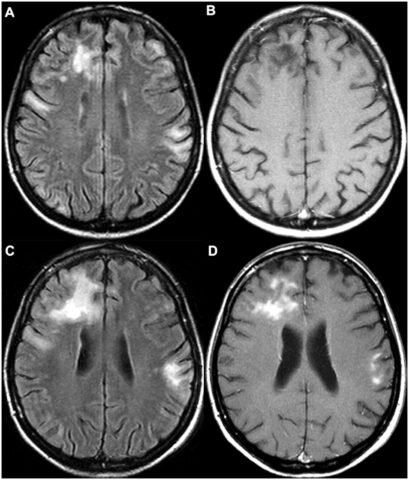

Для определения формы и стадии развития патологии делают томограмму сосудов головного мозга. В обязательном порядке проводится реоэнцефалография сосудов.

МРТ;